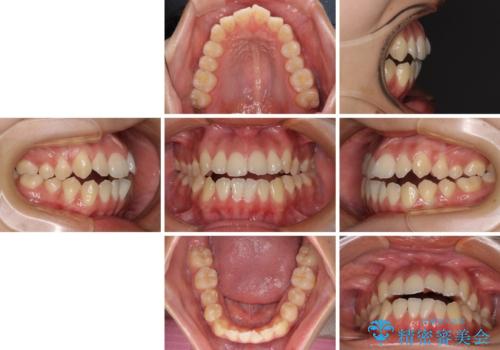

受け口と開咬を急速拡大装置とワイヤー装置で改善

- 20代女性

- メタルブラケット

- 1年3ヶ月

- 前歯の開咬と、受け口による咬み合わせの悪さを気にして来院された患者様です。

上顎歯列が狭窄していたため、急速拡大装置により上顎骨を側方に拡大し、その後ワイヤー装置にて矯正治療を行うこととしました。

舌の突出癖が開咬の原因であったので、改善のための舌トレーニングを行っていただきました。

舌トレーニングは後戻りにも大きく影響するため、とても重要なトレーニングです。